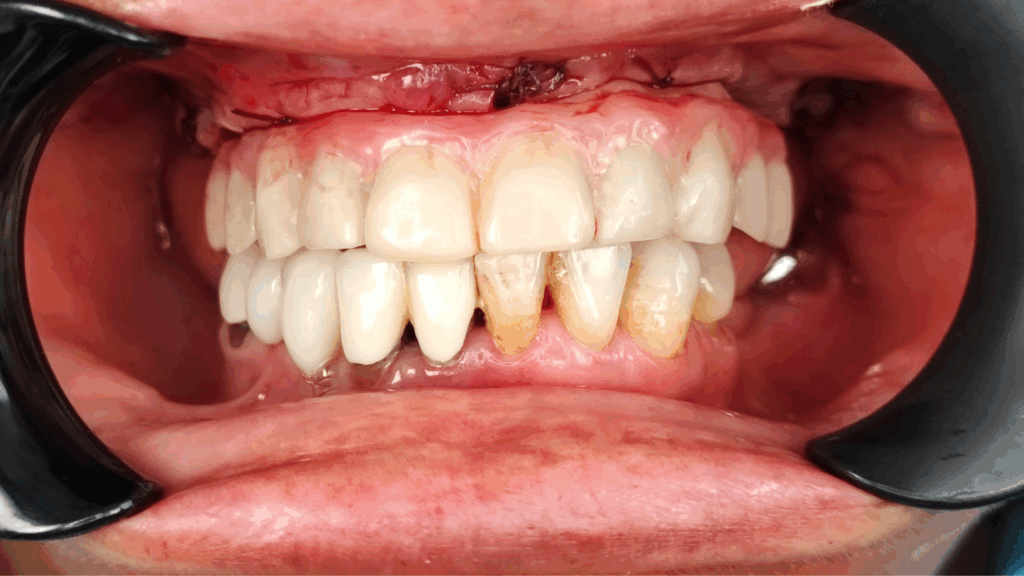

Rehabilitación completa maxilar (Full Arch)

Paciente: mujer, 59 años, edentulismo parcial.

Tratamiento: colocación de 6 implantes inmediatos con férulas apilables y prótesis provisional instantánea parcial.

Tiempo de intervención: 2 horas y 30 minutos.

Beneficios: intervención rápida y precisa, manejo conservador del tejido blando, estética y funcionalidad instantánea, alta satisfacción del paciente.

Estos casos ilustran cómo nuestro flujo BRDP y la cocreación clínica permiten resultados predecibles y eficientes, optimizando tanto el tiempo de sillón como la experiencia de paciente y clínica.